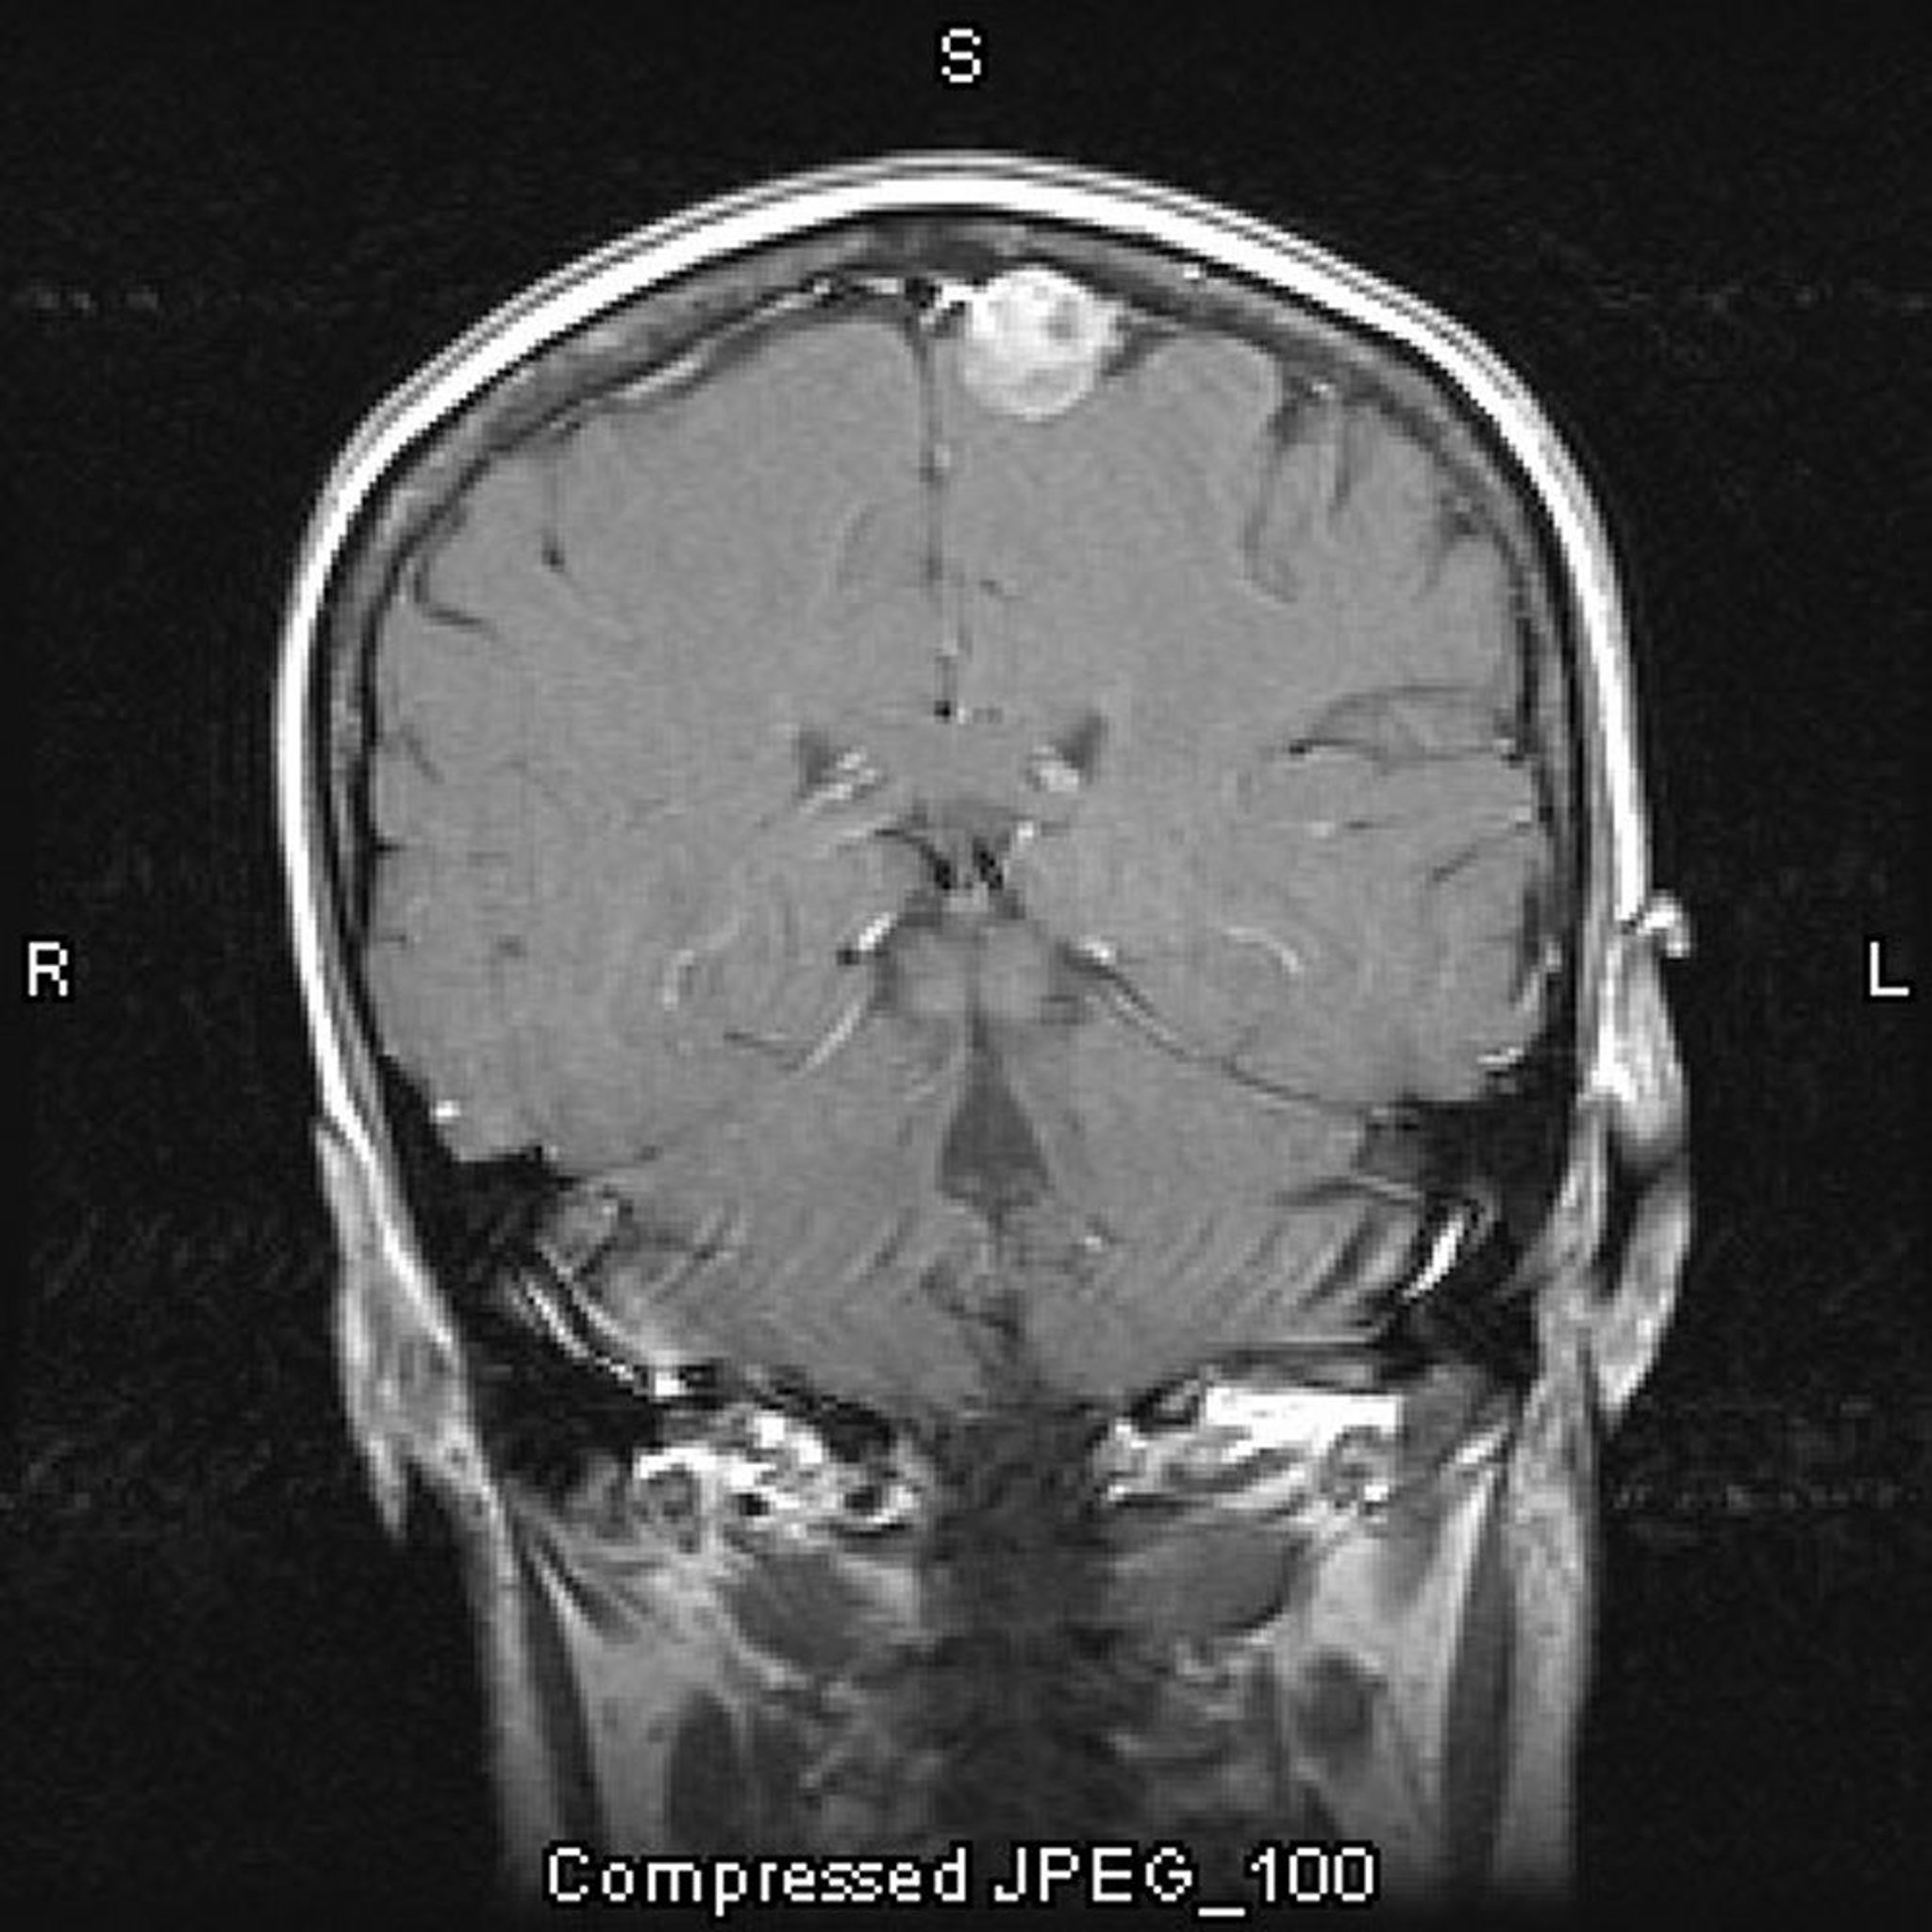

Meningioma parasagital

Este RM con contraste que muestra un meningioma. La ubicación parasagital es típica de los meningiomas.

Image courtesy of William R. Shapiro, MD.